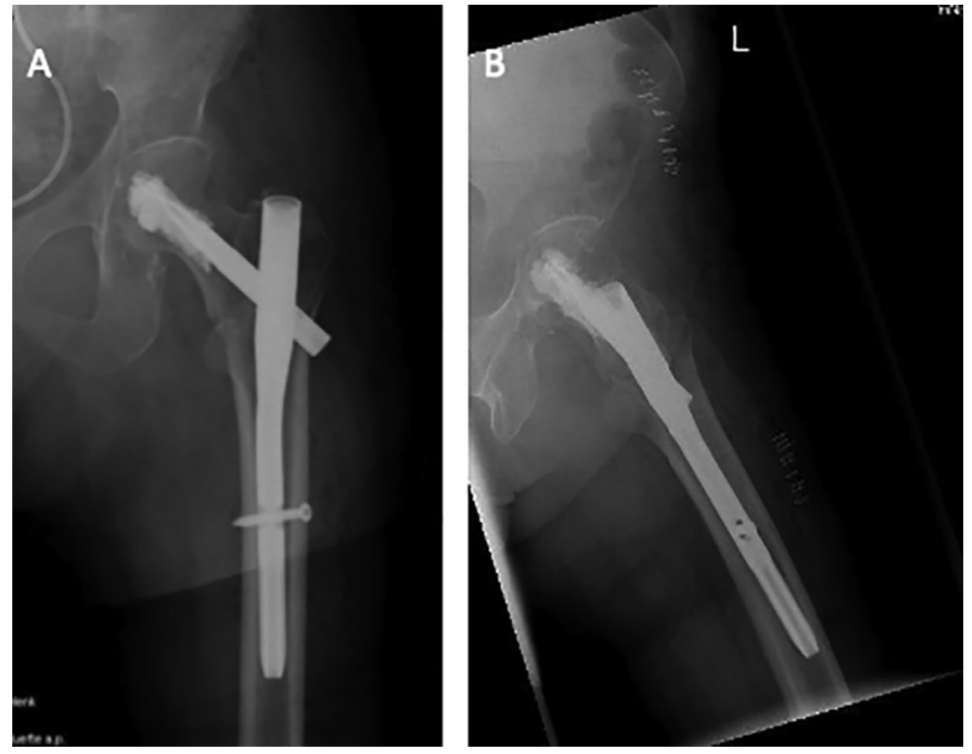

股骨近端骨折是老龄患者最常见的骨折之一,其中50%累及转子周围区域。老龄患者骨质疏松,PFNA内固定术后早期功能锻炼可能导致螺钉切割、内固定失效等并发症,而早期功能锻炼对患者功能恢复至关重要。因此,有学者研究了骨水泥加强的PFNA,以评估能否增加老龄患者患肢早期的负重能力。